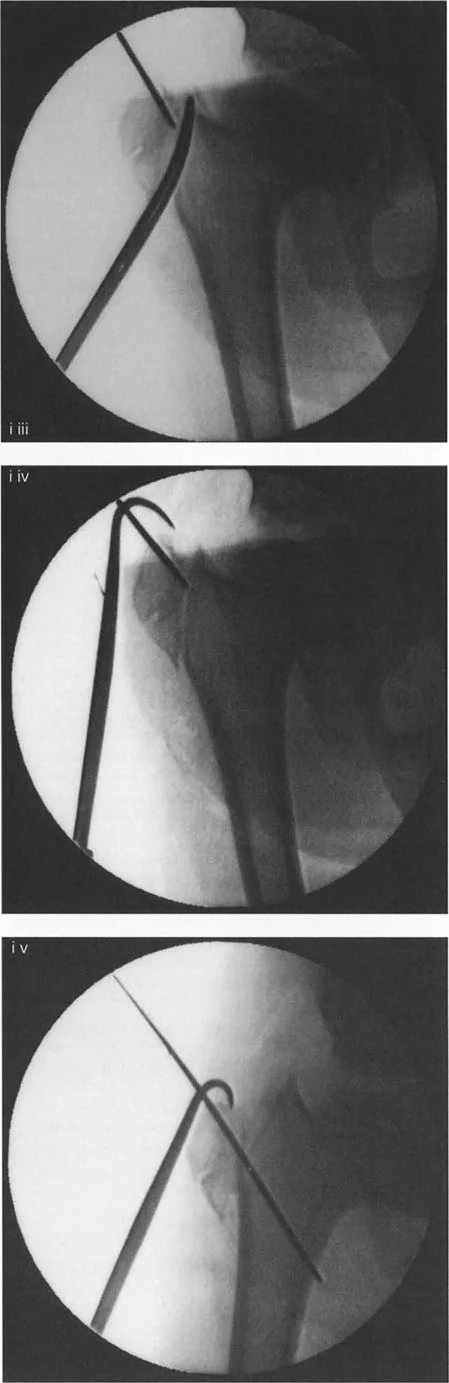

صور توضح حالة كسع الورك مع تضخم المدور الكبير قبل وبعد إجراء قطع عظم واغنر، حيث يتم تصحيح المحاذاة ونقل المدور الكبير.

- كيف يتم الإجراء (نقل المدور الكبير بالمنظار):

- يتم إدخال سلك توجيه في المدور الكبير لتحديد مسار القطع.

- يتم إجراء قطع عظمي حول قاعدة المدور الكبير باستخدام أداة خاصة (Osteotome).

- يتم تحرير الأنسجة الرخوة والعضلات المرتبطة بالمدور الكبير باستخدام أدوات جراحية دقيقة.

- باستخدام خطاف عظمي، يتم سحب المدور الكبير إلى الوضع المطلوب (عادةً إلى الأسفل والجانب).

- يتم تثبيت المدور الكبير في مكانه الجديد باستخدام مسامير خاصة (Cannulated Screws).

تسلسل صور بالأشعة السينية يوثق تقنية نقل المدور الكبير بالمنظار، من إدخال سلك التوجيه والقطع إلى التثبيت بالمسامير.